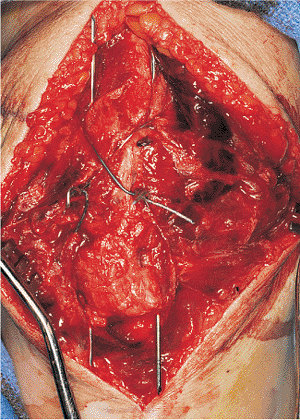

tension-band wire technique is performed. By using a 2-mm drill, two

parallel drill holes are placed in a retrograde fashion through the

proximal bony fragment. A 1.6- or 1.8-mm K wire is then advanced

through these holes and out through the quadriceps tendon (Fig. 24.4).

They are advanced until the sharp tip of the K wire is fully within the

proximal bony fragment. The two fracture fragments are then reduced and

held with large, pointed, reduction forceps.

![]() |

|

Figure 24.4.

The hematoma has been evacuated, and the joint and fracture lines have been debrided. The K wires have been advanced retrograde through the patella, and the patella fragments are now ready to be reduced. |